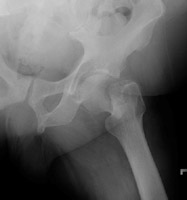

- Click on the image for a larger versionCAP radiograph of the pelvis. This is a different patient with prostate cancer. There are multiple sclerotic metastases.

- Click on the image for a larger versionDAP radiograph of the left hip. Two years later, the patient presents with hip pain and a femoral neck fracture (basicervical).